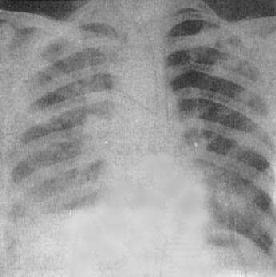

(1)一侧性肺不张:X线现为患侧肺野均匀致密,纵隔向患侧移位,肋间隙变窄(图3-1-7)。健侧肺可有代偿性肺气肿。

图3-1-7 一侧性肺不张

左侧支气管阻塞引起左侧全肺不张,显示左侧肺野均匀致密,

纵隔向患侧移位,肋间隙变窄,膈升高